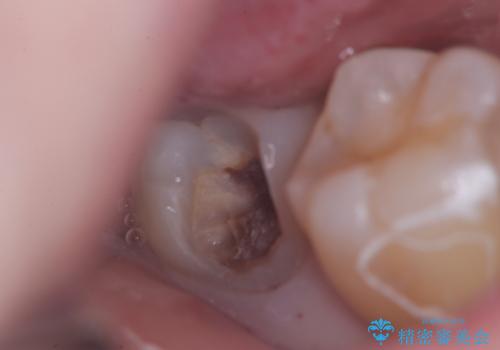

- 頬側に大きな虫歯があり、神経に達している可能性が高かったため、虫歯除去時に神経が出た場合はVPTを提案しました。

虫歯が神経まで達していましたが、術前の検査でVPTの適応と診断をしていたので、ラバーダムシートを装着しVPTを行いました。